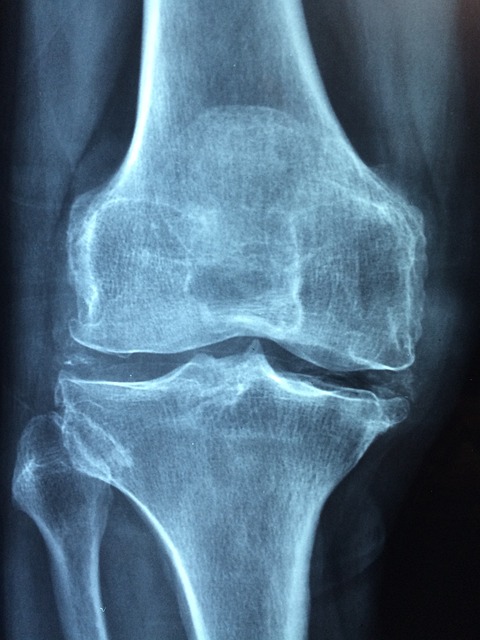

| 관절 통증 완화를 위한 운동과 식이요법 (0) | 2025.06.06 |